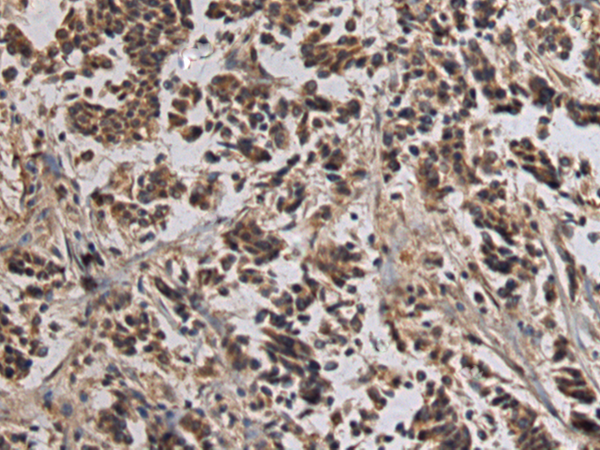

IHC positive control: |

Human breast cancer |

IHC Recommend dilution: |

100-300 |